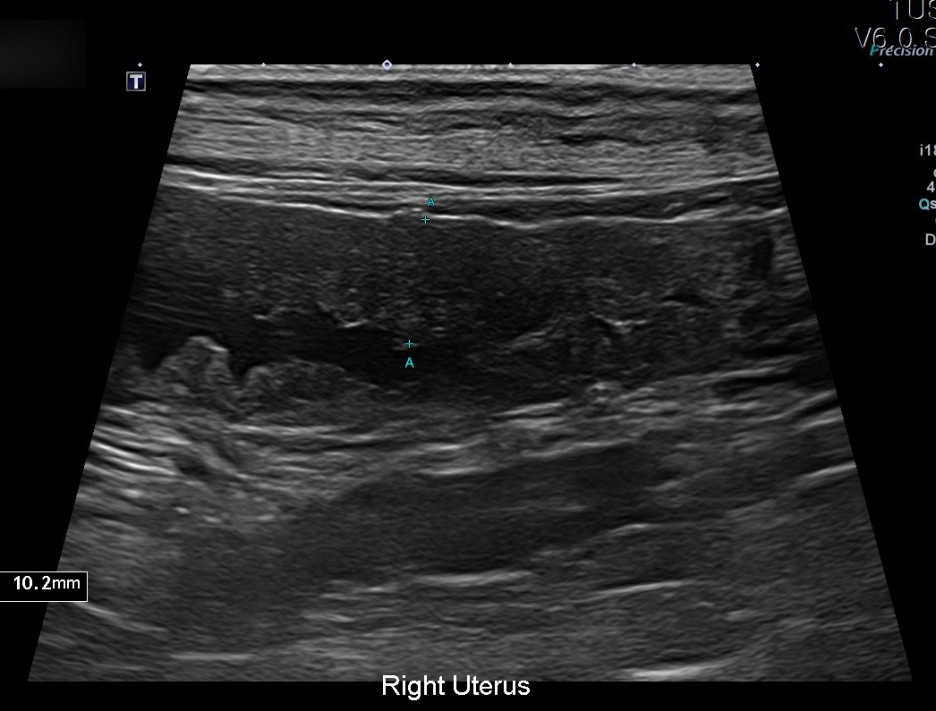

이어 진행된 초음파 검사에서는 자궁축농증으로 인해 내막이 두꺼워지고 크기가 커지는 염증성 변화가 진행되고 있었습니다.

✔US 양 자궁내막증식, 자궁각내삼출물에 의한 심한 확장소견